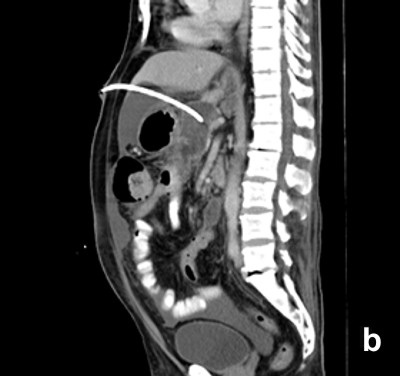

Twenty-four patients (48.0%) underwent image-guided drainage of the pancreatic/peripancreatic collections. Nine of these patients (37.5%) were successfully managed by radiological intervention only (Figure 2) while 15 (62.50%) continued to have or developed infection, persistent organ failure or locoregional complications. These 15 patients were subsequently operated upon (Figure 3). There were a total of 11 procedure-related complications in these patients (73.3%) with two patients having catheter slippage which required repositioning (Table 1).

Figure 3. a. Well-defined collection within the pancreas in a patient with gallstone-induced pancreatitis on the 21st day (nasojejunal tube is seen in the duodenum). b. Percutaneous catheter inserted the next day. c. Sixteen days later, the collection showed regression but the inflammation persisted. The patient had deteriorated and was operated on. |